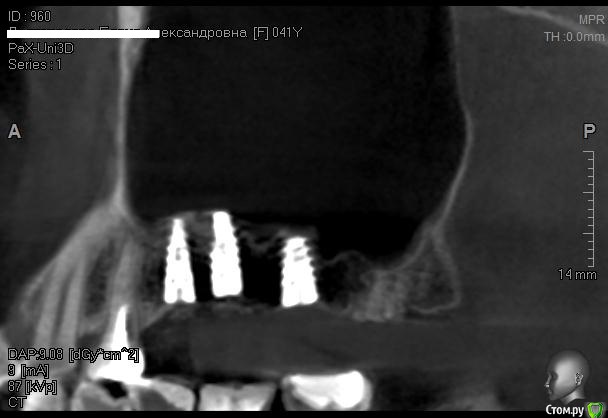

Kostoprav Опубликовано 9 июня, 2014 Поделиться Опубликовано 9 июня, 2014 Решил попробовать бюджетный материал , может кто нибудь с ним уже сталкивался? 2 Ссылка на комментарий

Kostoprav Опубликовано 30 мая, 2015 Автор Поделиться Опубликовано 30 мая, 2015 все работает, чистая синтетика без ауто! это не единичный случай. 2 Ссылка на комментарий